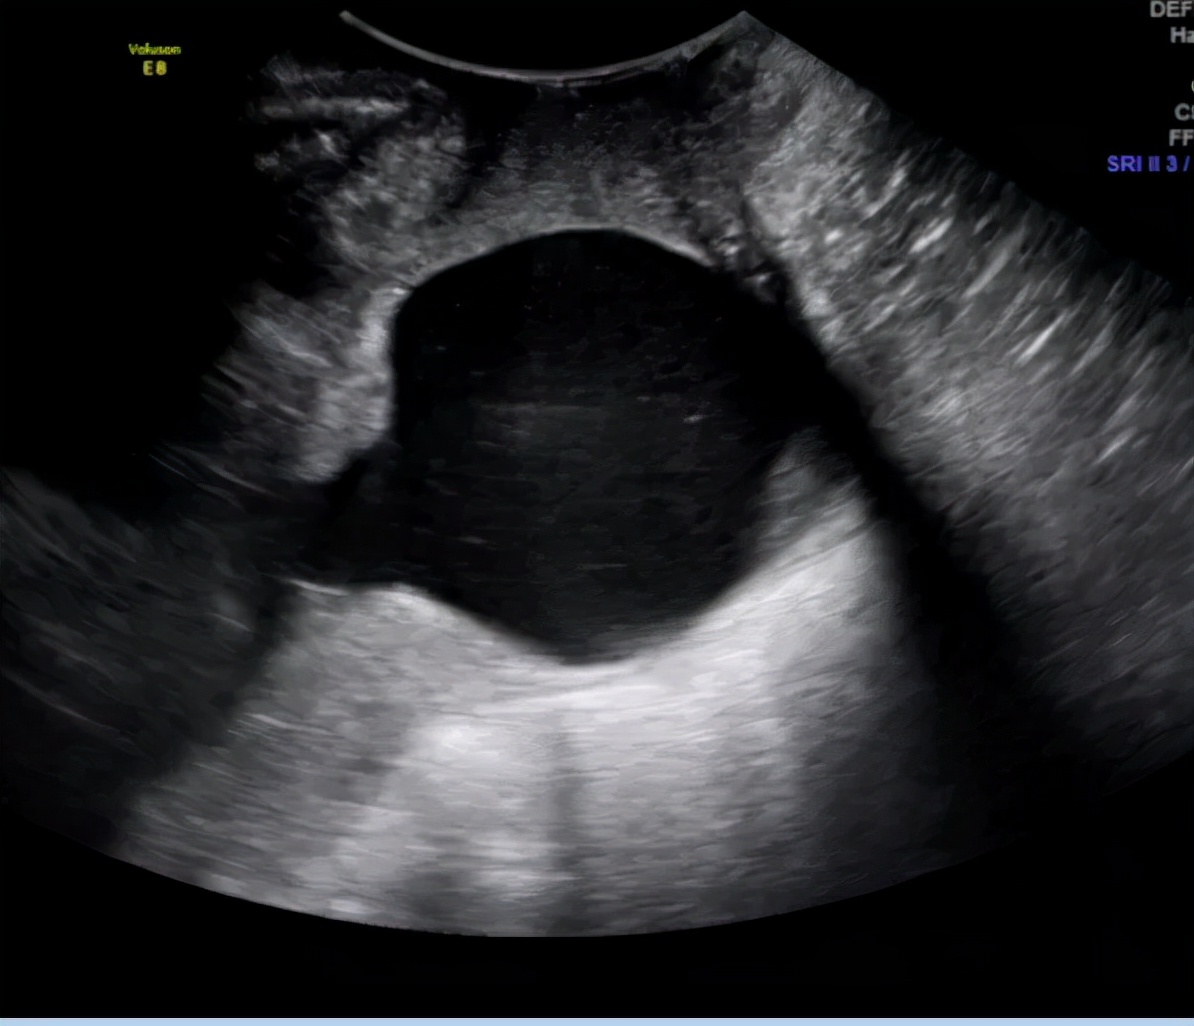

近日,一位怀有双胎的37岁的女士因持续一夜的下腹部坠痛来到医院急诊。经紧急超声检测宫颈长度,超声医师发现这位女士宫颈全开并且羊膜已突进宫颈内。这位女士是典型的宫颈机能不全,但因错过了最佳就诊时机,最终这位女士不幸流产。其实如果能早一些按照医嘱定期进行宫颈长度的测量,或是疼痛刚一发生时及时就诊,或许可以避免悲剧的发生。

经阴道测量 是测量宫颈长度的首选方法,经阴道超声检查的超声图像可视性较好,测量结果可重复性高且可靠,并且对预测自发性早产更敏感。经阴道超声检查被认为是评估宫颈长度预测早产的金标准。